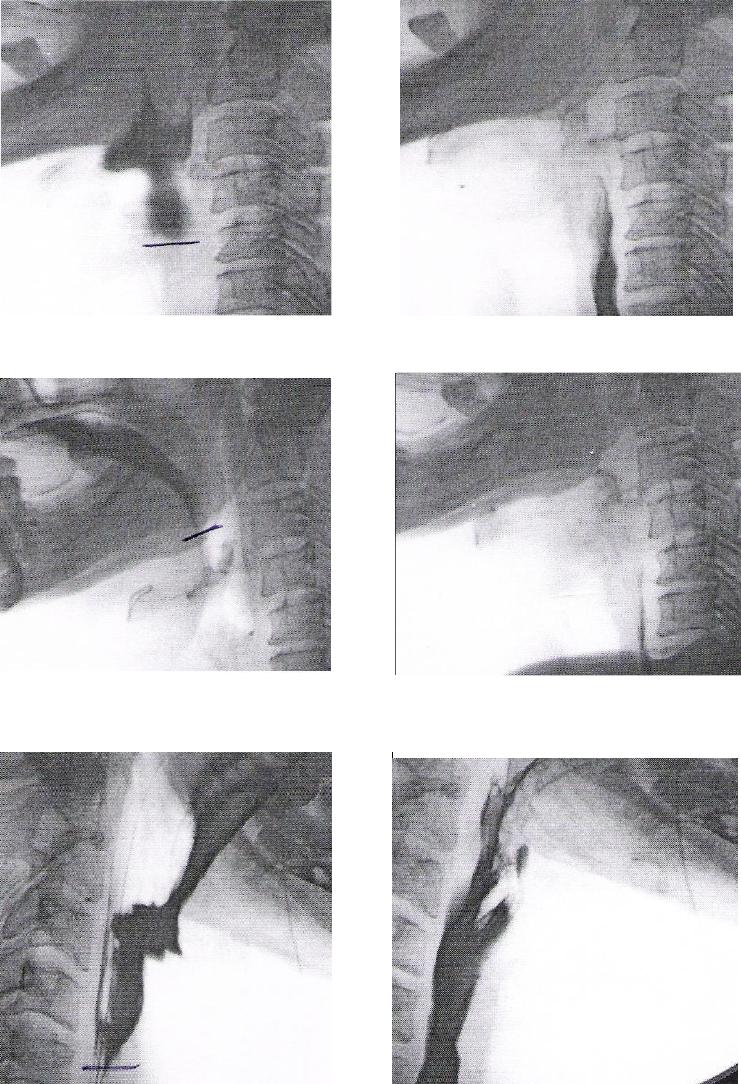

ANEXO E Imagens videofluoroscópicas da deglutição, registrando

escape prematuro e reação de deglutição atrasada, p e s

crioestimulação, com líquido e pastoso.........................................................